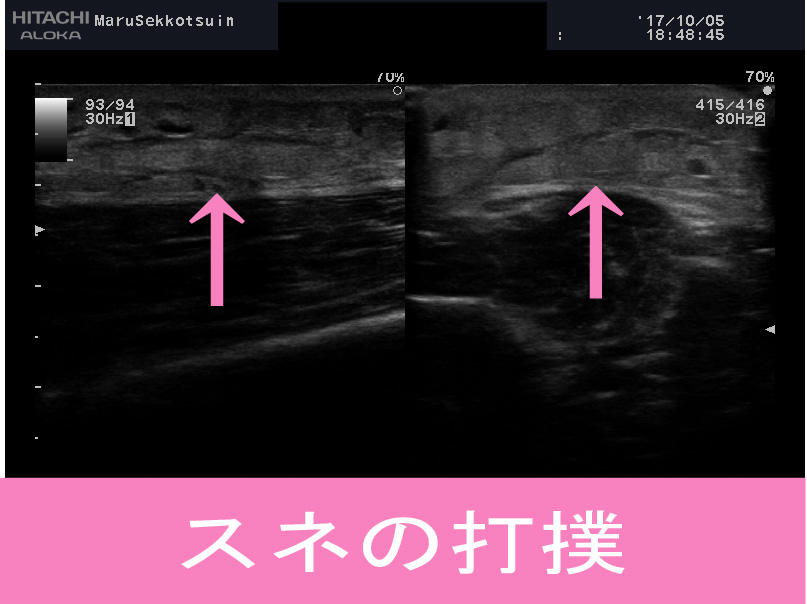

足首の捻挫、スネの打撲、はたまた鎖骨の骨折と、

「まる接骨院」ではしっかりと負傷箇所を、

エコー(超音波画像観察装置)で視的に確認し、

的確に治療を行い、早期回復・復帰の、

お手伝いをさせて頂いております。